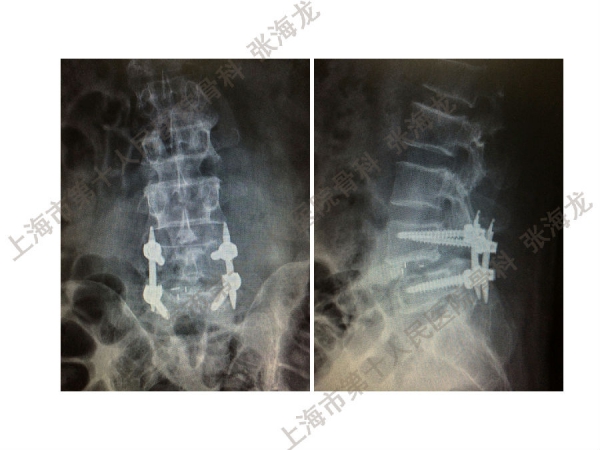

2008年3月至2010年8月,上海市第十人民医院骨科随访49例腰椎滑脱症(峡部裂型和退变型)患者,对比23例微创手术MIS-TLIF和26例开放手术治疗腰椎滑脱症的临床及影像学结果,进行了回顾性研究。

研究发现,Wiltse入路Mis-TLIF更直接的暴露峡部及关节突,对脊柱稳定性的影响较小;彻底松解辅助双重提拉复位Mis-TLIF,对于峡部裂型滑脱有较好的复位效果;对于峡部裂型滑脱,提拉复位在影像学参数上有一定优势;与原位融合相比,ODI.VAS.JOA无明显差异(样本量有限);对于退变性滑脱,单纯撑开椎间隙与原位融合可以获得较好疗效。